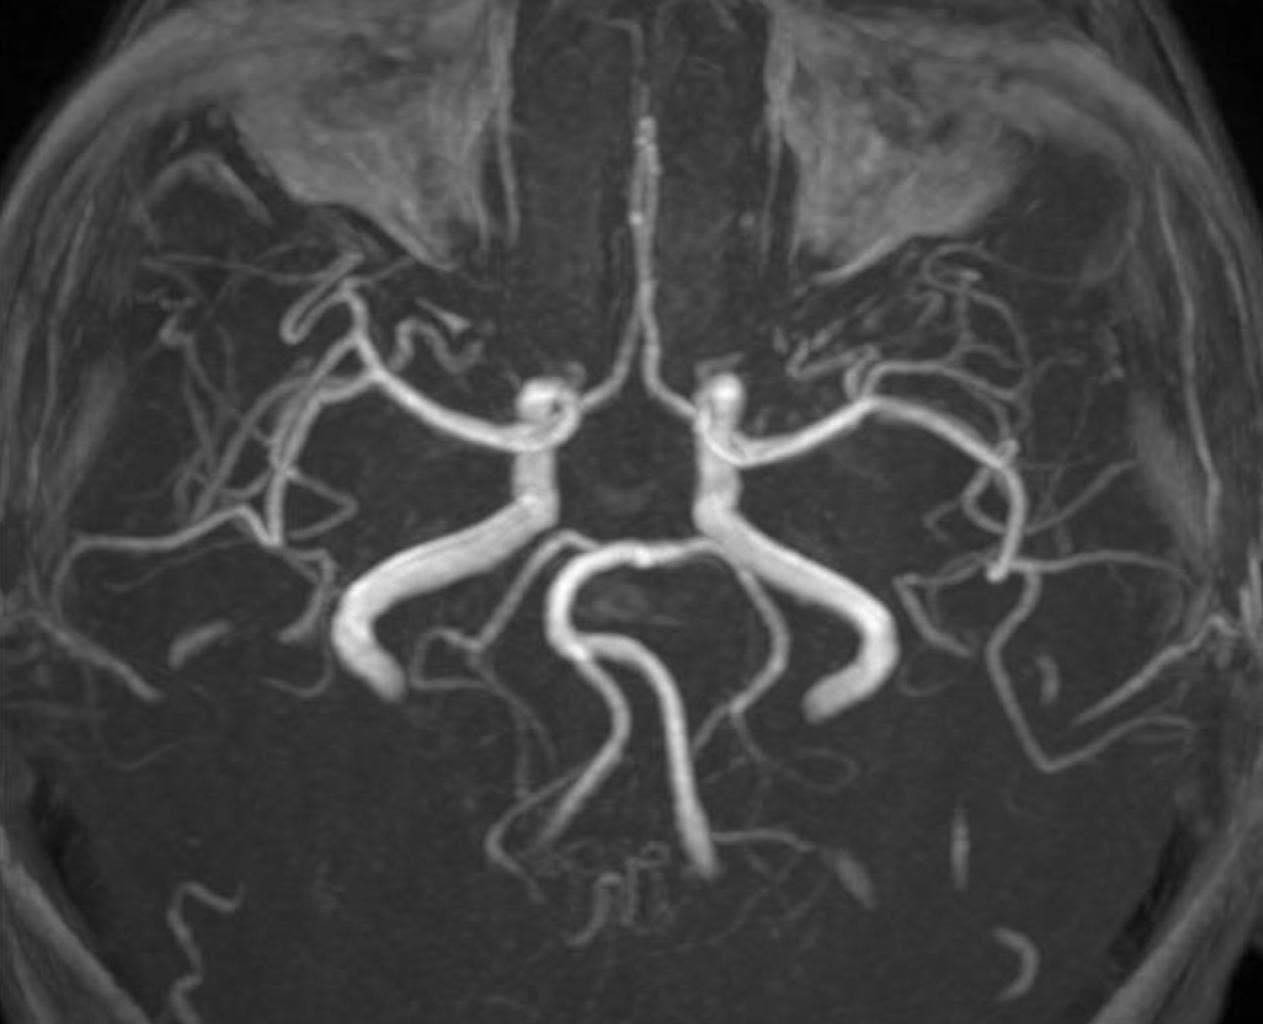

PGS Huy Thắng cho biết, ngay khi nhập viện, người bệnh được chụp MRI não. Hình ảnh cho thấy tổn thương não xảy ra ở hai bên trung tâm bán bầu dục và vùng lồi thể chai. Các thăm dò mạch máu não không ghi nhận tình trạng tắc hay hẹp các động mạch lớn. Dựa trên lâm sàng và hình ảnh học, các bác sĩ chẩn đoán bệnh nhân bị nhồi máu não cấp vùng trung tâm bán bầu dục hai bên và lồi thể chai.

Nữ bệnh nhân đột quỵ bác sĩ chỉ ra nguyên nhân bất ngờ- Ảnh 2.

Hình ảnh kiểm tra mạch máu não của người bệnh không ghi nhận tình trạng tắc hoặc hẹp các mạch máu lớn (ảnh: BSCC)